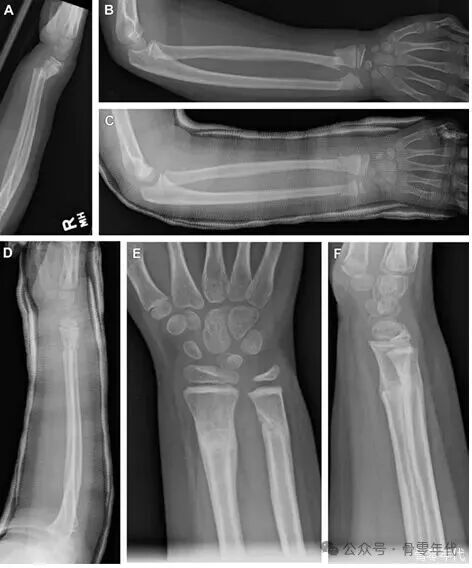

一名5岁女童从三轮车上摔下,导致远端桡骨和尺骨骨折(A、B)。该儿童在急诊室接受了闭合复位和石膏固定。两周后的随访X光显示复位良好(C、D)。受伤八周后,X光显示骨折已愈合,解剖对位良好(E、F)。

Galeazzi损伤:一名10岁男孩从滑板上摔下,导致远端尺骨骨骺发生Salter-Harris 4型骨折,并伴有桡尺远端关节(DRUJ)损伤(A、B)。随后患者接受了DRUJ的钢针固定(C、D)。3个月随访X光片(E、F)。